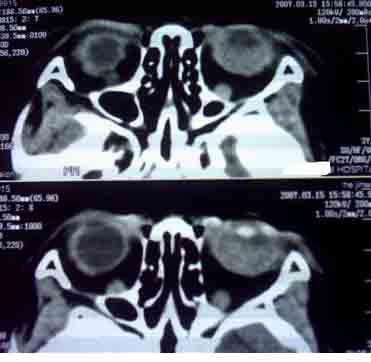

患者,偶然发现左眼无光感,平时,无明显不适,眼外观无明显异常。

首先考虑视网膜母细胞瘤。

支持左侧视网膜母细胞瘤,可惜没有钙化。

大家有没有想到有哪些需同成视网膜细胞瘤鉴别诊断的疾病?正是没有钙化,所以此病首先更应该考虑什么?请大家说说看。

考虑左侧眼球渗出增殖性视网膜炎所致视网膜剥离,建议mri检查。

1.ct表现:眼球内均匀高密度肿块,有增强,并多有点状或团块状钙化,在3岁以下的儿童有极大的诊断价值。可见相关视网膜下积液。

2.mr表现:肿瘤t1加权像为较视网膜略高或与视网膜相等的信号强度,t2加权像为低信号强度。大钙斑t1、t2加权像均为低信号斑,小钙斑不易显示。视网膜下积液或积血显示清楚。

鉴别诊断 :需与渗出性视网膜病鉴别。